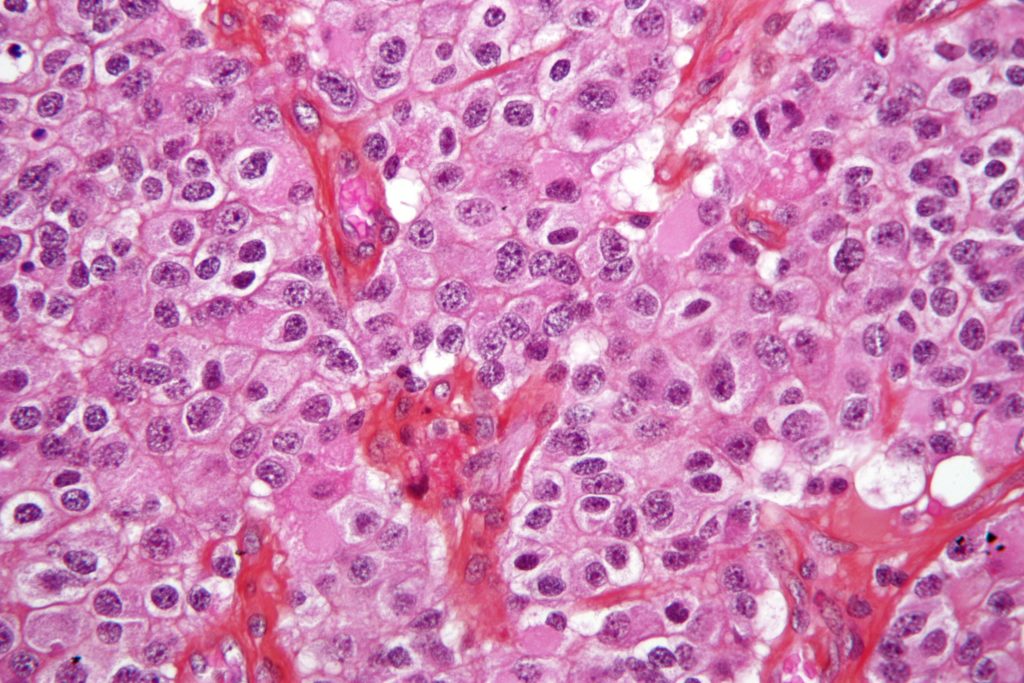

El oligodendroglioma es un tumor primario del sistema nervioso central que se origina en el cerebro o en la médula espinal. Afecta principalmente a personas de entre 35 y 44 años. Entre los síntomas más frecuentes se encuentran convulsiones, dolor de cabeza, alteraciones de la memoria y del pensamiento, debilidad, entumecimiento y problemas de equilibrio.